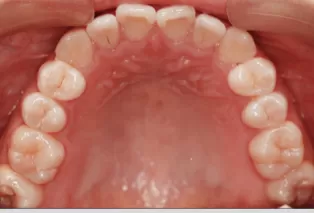

Intraoral photos